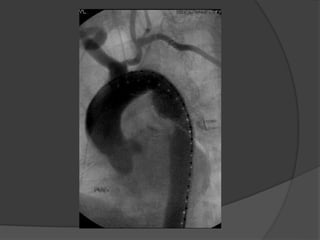

Cas 1

 Reparation par stages (3) et trois admissions.

 Stage 1: transposition carotido-sousclavien

gauche

 Stage 2: Pontage carotido-sousclavien droit

(Gore Tex)

 Stage 3: TEVAR (Zenith TX2)

- transfemoral

- pacemaker transveneux ventriculaire

durant placement du stent thoracique

Suites Post-operatoires: CTA

 Aucunes

endofuites ou

migration

 Exclusion

complete et

thrombose de

artere lusorienne

ainsi que le

diverticule